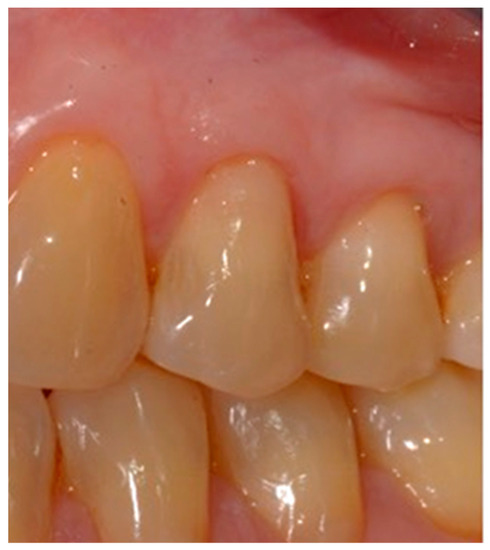

- Selection of the shades (dentinal masses and enamel) of the tooth to be restored (Figure 1);

- Initial measurement of the length of the clinical dental crown (performed with a millimeter periodontal probe placed adjacent to the dental crown and having as a reference the most apical part of the gingival sulcus and the highest part of the crown) and photography of the lesions at time 0 (t0) (Figure 2a).